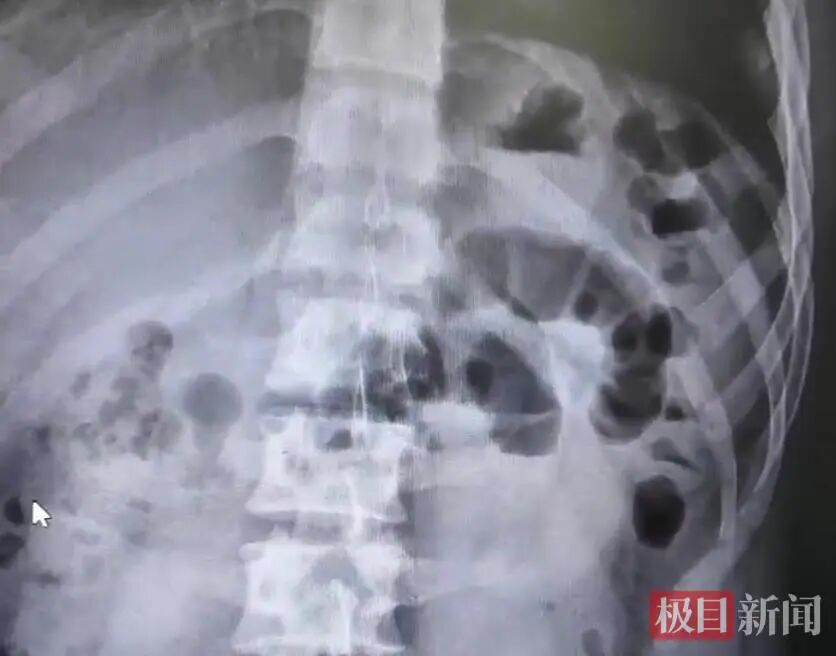

CT检查(受访者供图)

流程腹部CT检查,李阳被确诊为典型小肠壅塞,病因恰是短时辰内过量进食胡萝卜,肠谈堵塞。